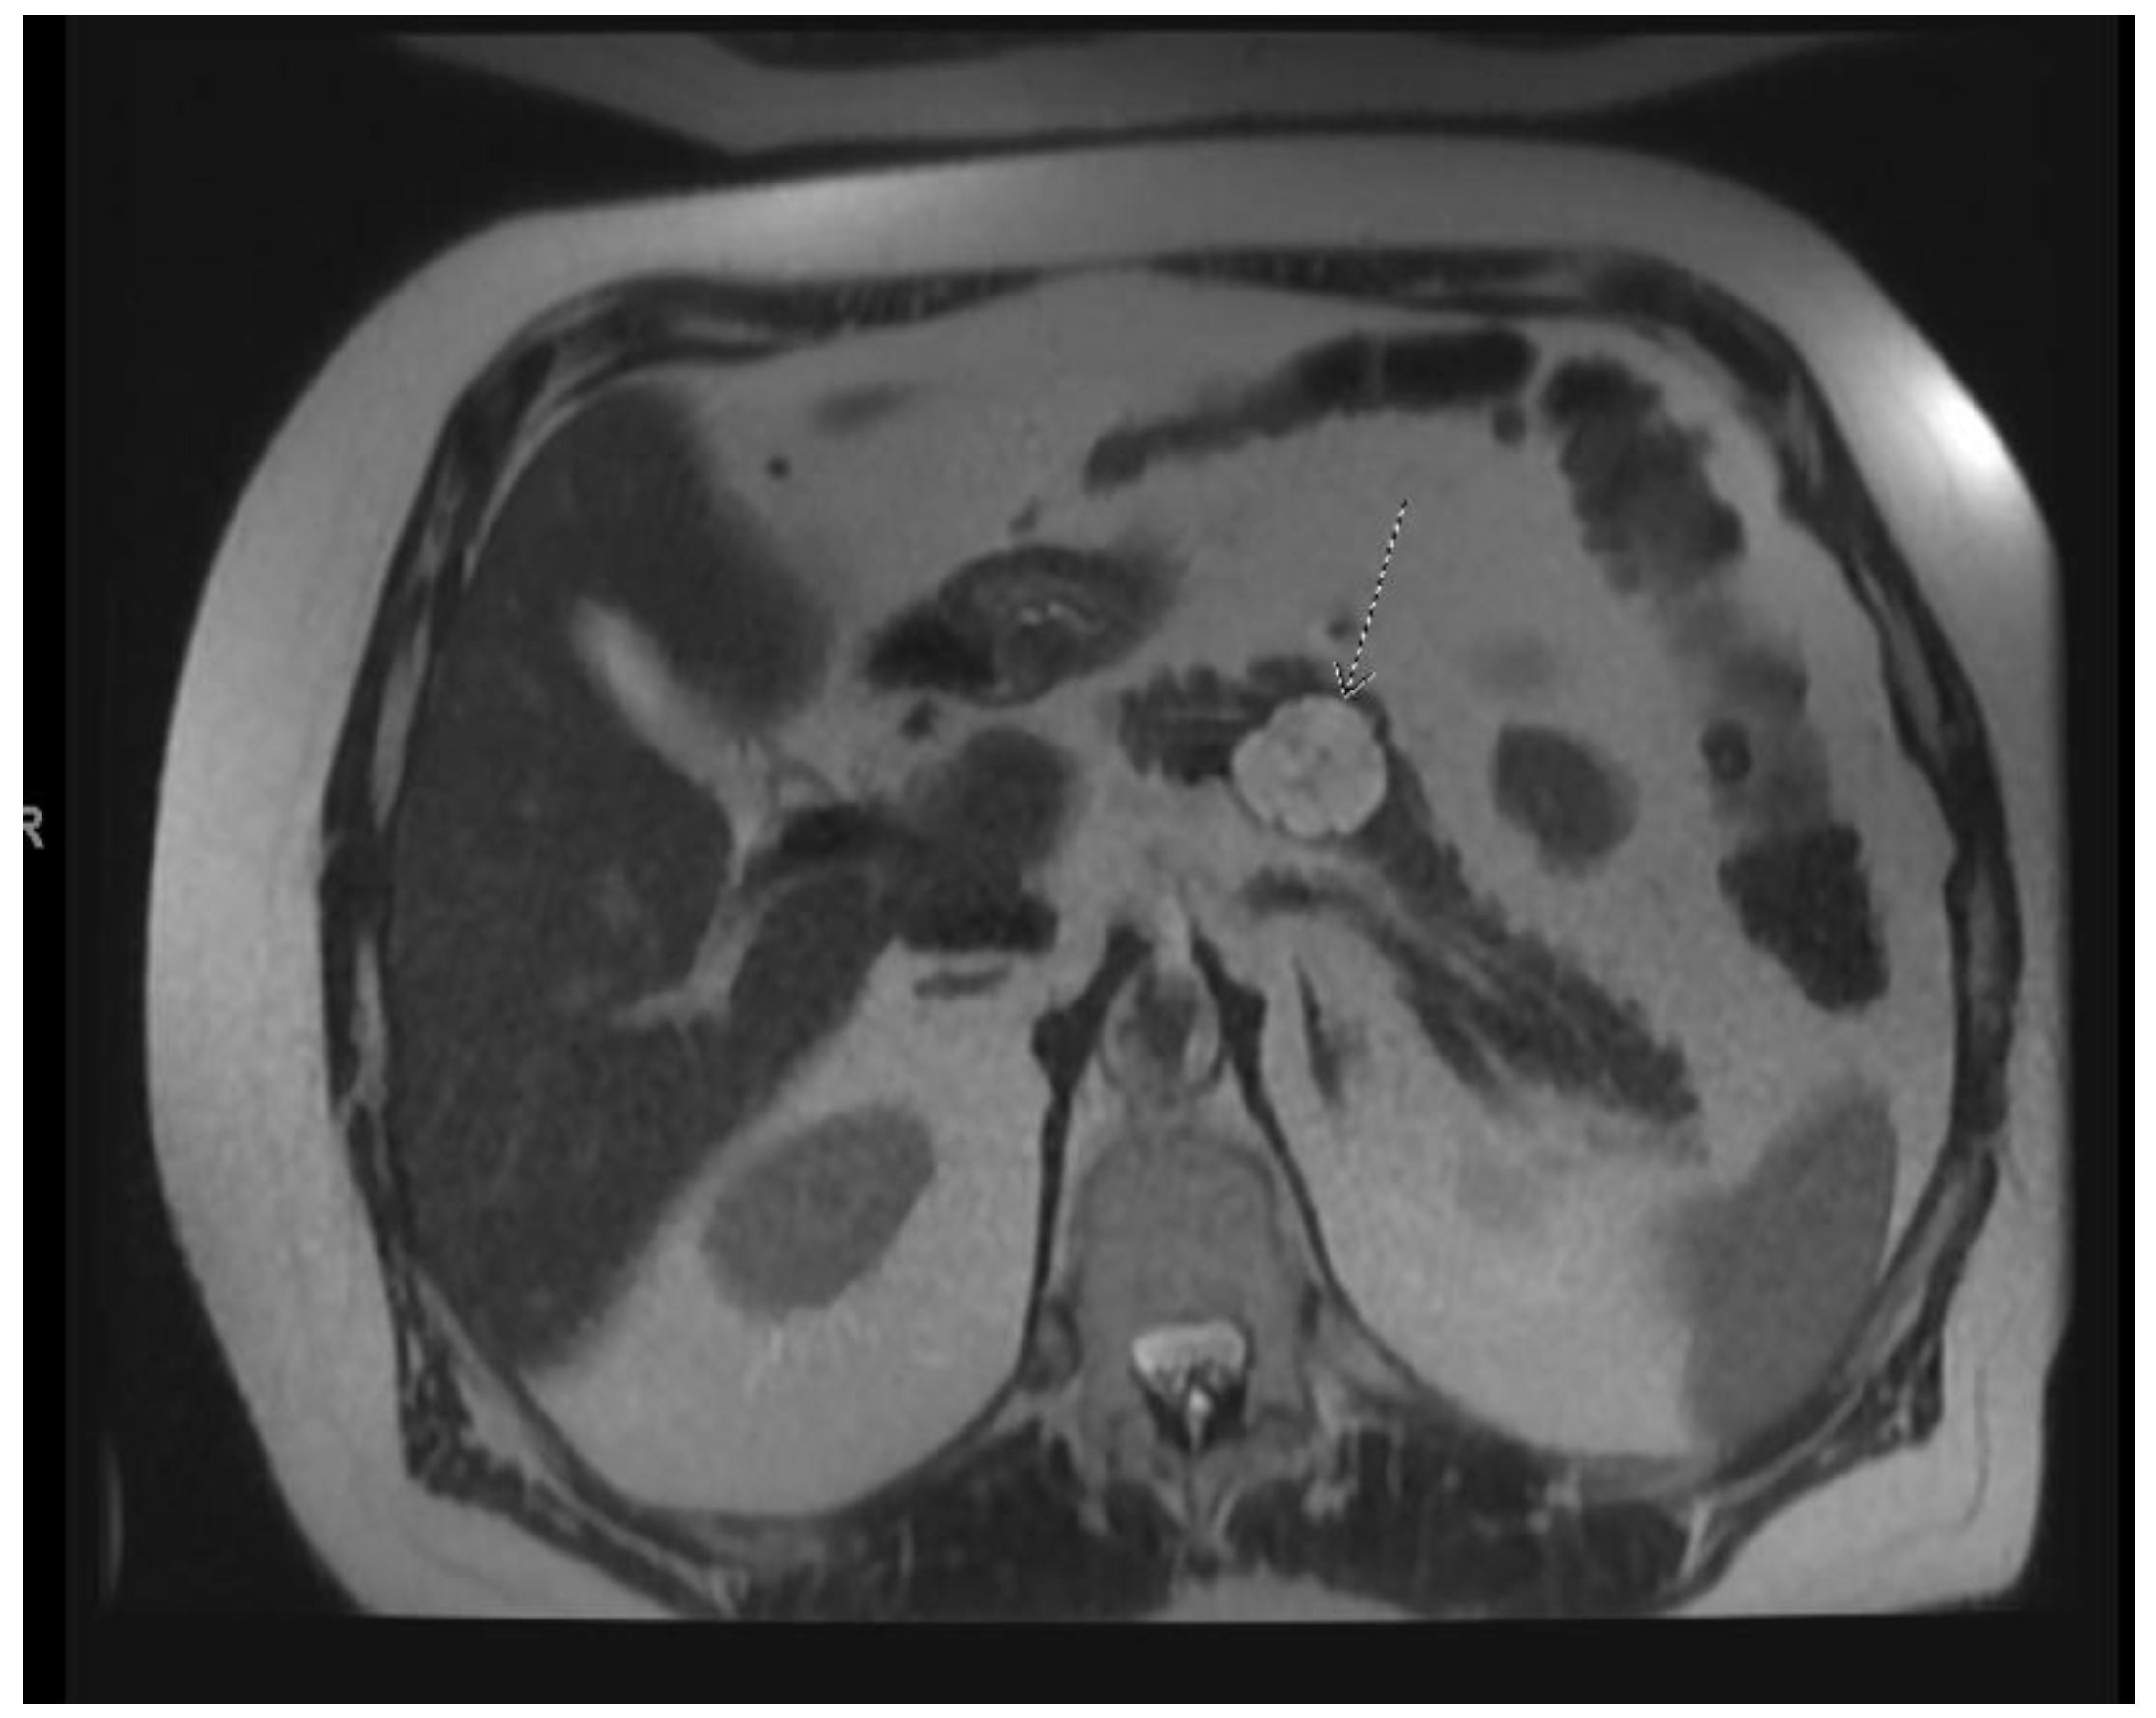

Figure 5.

T2 weighted MRI of the abdomen demonstrating a serous cystic neoplasm with a central scar.